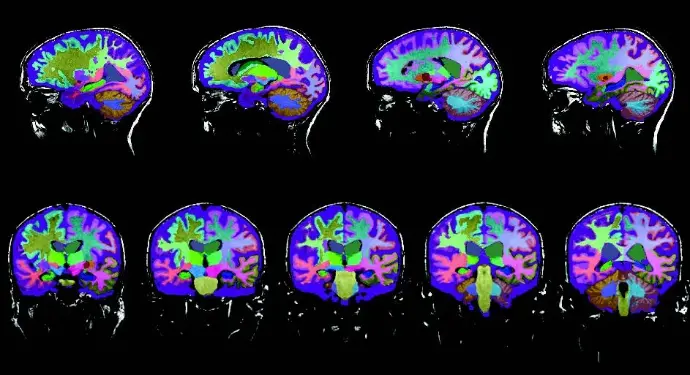

Neuroreader® has been independently validated in peer-reviewed research and clinical practice as a reliable, FDA-cleared tool for fast and accurate brain volumetric analysis. Dr. Cyrus A. Raji demonstrates how to interpret Neuroreader® Reports in the following clinical case studies.

A 78-year-old woman presented with progressive memory loss. To support clinical evaluation, her physician ordered a 3D T1 volumetric MRI sequence, which was analyzed using Neuroreader®, an advanced software for automated brain volumetry. The Neuroreader® Report provided objective, quantitative insights into her brain structure volumes, helping guide a more accurate diagnosis of Alzheimer’s dementia.

A 69-year-old woman with memory loss and depression underwent four MRI scans over seven years (ages 62, 64, 66, and 69). Using Neuroreader® volumetric software, progressive changes were quantified and tracked across key brain regions.

This video presents a real-world Neuroreader® case review designed for clinicians and imaging specialists. Through guided interpretation and expert commentary, viewers gain hands-on insight into using brain volumetrics for early detection, differential diagnosis, and tracking neurological disorder progression. The session emphasizes how quantitative brain measurements improve diagnostic confidence and enhance patient management.